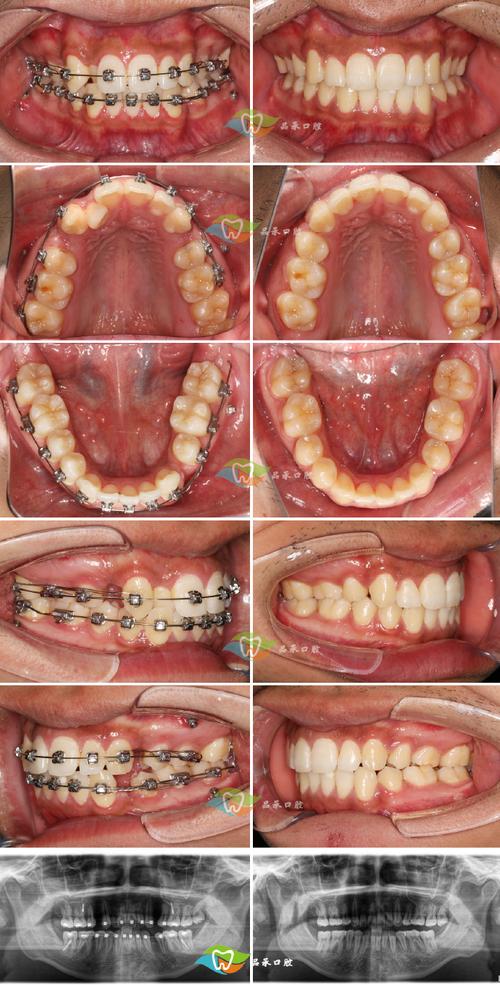

典型病例展示:正畸拔除下颌4颗前磨牙(4号、5号牙)

患者信息: (为保护隐私,使用化名) 小李,男,16岁 主诉: 下牙拥挤不齐,感觉“地包天”(实际是下颌前牙前突,非真性反颌),希望改善。 初始检查:

- 口内照:

- 下颌牙列: 严重的牙列拥挤,下颌前牙(尤其是中切牙)明显前突、扭转、重叠,下颌第一磨牙为中性关系。

- 上颌牙列: 上颌前牙也稍显前突,牙列轻度拥挤。

- 咬合: 前牙深覆盖(上切牙盖过下切牙较多),前牙深覆合(上切牙盖过下切牙垂直距离大),下颌尖牙咬在上颌第一前磨牙颊尖的远中,存在部分Ⅱ类磨牙关系(下颌第一磨牙近中颊尖咬在上颌第一磨牙的近中颊沟)。

- 中线: 上下颌中线基本一致。

- X光片(全景片 & 头颅侧位片):

- 全景片: 下颌牙弓严重拥挤,下颌智齿已萌出或近中阻生,牙根形态良好。

治疗过程展示:

- 照片: 展示初始的口内照(上下颌拥挤、前突)和面部照(凸面型)。

- X光片: 展示初始全景片和头颅侧位片,标记计划拔除的牙齿(下颌34, 35, 44, 45;上颌14, 24)。

- 照片: 展示拔牙创口愈合良好,粘接矫治器后的口内照,可见拔牙间隙(下颌第一、二前磨牙拔除处)。

- 照片:

- 口内照: 上下颌牙齿逐渐排齐,扭转、倾斜的牙齿被纠正,拔牙间隙开始缩小(下颌)。

- X光片: 可见牙齿在牙槽骨中移动的轨迹,牙根平行度改善。

- 口内照: 牙齿排列整齐,上下颌中线对齐,下颌拔牙间隙完全关闭,前牙覆盖、覆合显著减小,达到正常范围,尖牙建立稳定引导,磨牙达到中性关系。

- 口内照: 拆除矫治器后,佩戴保持器(通常为上颌 Hawley 保持器 + 下颌透明压膜保持器或舌侧丝保持器),牙齿排列整齐,咬合关系良好。

- X光片: 保持期复查,牙根位置稳定,牙槽骨改建良好。

最终效果展示 (T4 - 保持期稳定后)

- 口内照对比 (初始 vs :

- 下颌: 从严重拥挤、前突、扭转变为排列整齐、整齐的牙弓,前牙位置内收,覆盖覆合正常。

- 上颌: 从轻度拥挤、前突变为排列整齐,前牙位置内收。

- 咬合: 建立了稳定的尖牙引导和磨牙中性关系,咬合广泛接触。

- X光片对比 (头颅侧位片):

- 上下颌切牙突度(U1-NA, L1-NB)显著减小,位置更直立。

- 覆盖(Overjet)和覆合(Overbite)恢复正常。

- 面部软组织轮廓改善,鼻唇颏角更协调。

- 模型对比: 上下颌模型排列整齐, Bolton指数匹配良好。